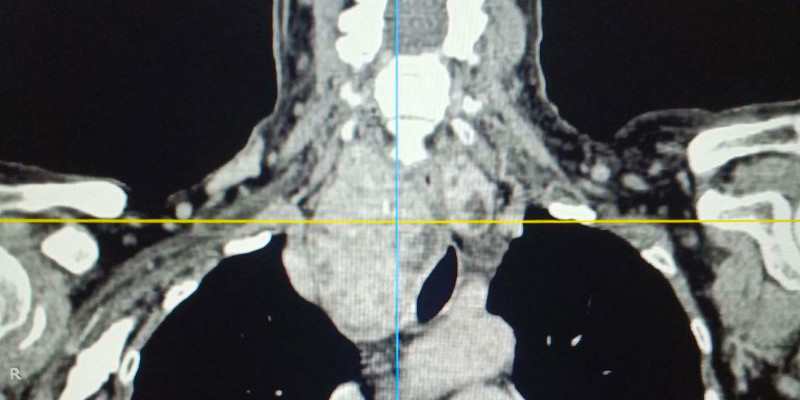

Особую сложность представляло анатомическое расположение зоба. По словам хирурга, расположение зоба было частично загрудинным, образование опускалось за грудину примерно на две трети. А правая доля щитовидной железы подходила вплотную к плечеголовному стволу — крупному артериальному сосуду. Кроме того, зоб циркулярно охватывал трахею, сдавливая ее со всех сторон и вызывая у пациентки затруднение дыхания даже при небольшой физической нагрузке.

Операции предшествовало комплексное обследование, включавшее компьютерную и магнитно-резонансную томографию, в результате которых было принято решение о проведении срочного хирургического вмешательства. В настоящий момент состояние пациентки стабилизировалось, она чувствует себя хорошо выписана домой для дальнейшей реабилитации.